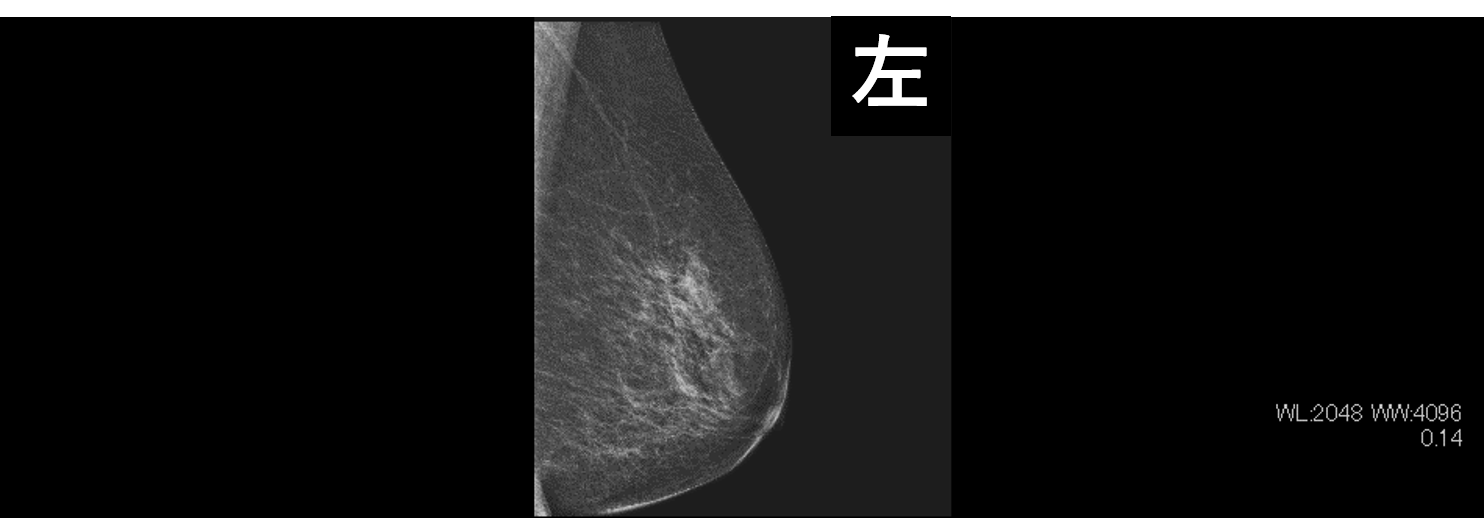

乳房専用のX線撮影検査になります。乳房全体を圧迫し、薄く伸ばした状態で撮影します。乳房を薄く伸ばすことで正常な乳腺の重さが少なくなり、腫瘤の形状や辺縁が観察しやすくなります。マンモグラフィは、乳房を触ってもわからないようなタイプの乳がん(石灰化病変)を描出することに優れています。

右乳房に腫瘤が2つ描出されている。